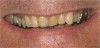

Figure  3  Severe dental erosion and attrition in a GERD patient.

Figure 3